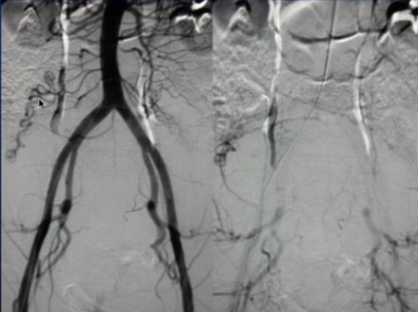

所有年龄超过 40 岁的患者, 卵巢受损 14%-43% 研究中闭经发生率(15%)与单纯UAE报告相似,可能与患者年龄(≥45岁)及卵巢储备自然下降有关。 ![]() 50岁,长期因子宫肌瘤导致月经出血过多,痛经和贫血。 子宫肌瘤栓塞术前,显示双侧子宫动脉发育不全,子宫肌瘤双侧卵巢动脉。 经皮股动脉穿刺双侧卵巢动脉栓塞,先500μm-700μm emboSphere 微球 术后4周,和6月的中短期随访,月经正常,子宫容积减少,贫血纠正,无卵巢功能衰竭。但看起来非灌注容积较少。 术后9月,由于子宫肌瘤持续存在,患者自己希望绝经,行全子宫和双侧卵巢切除术 术后病理,子宫内可见栓塞微粒伴有坏死,卵巢内也见栓塞微粒,但卵巢功能未受损。

双侧卵巢动脉栓塞术在选择性病例(如子宫动脉发育不全、卵巢动脉为主要血供)中是可行且有效的。

未引起卵巢功能衰竭,说明技术安全。